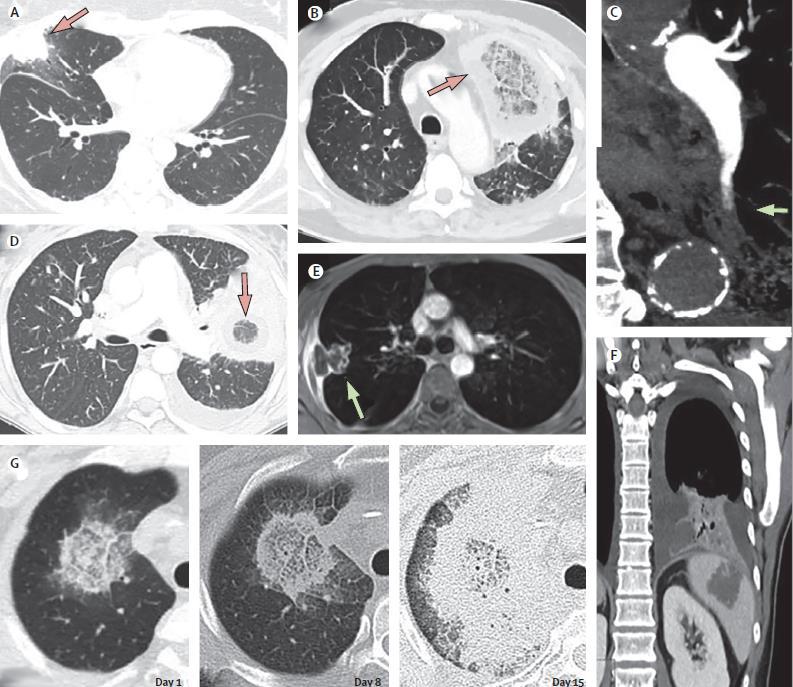

图:肿瘤患者接受化疗存在严重和长期的中性粒细胞减少,且影像学上表现为结节周围存在环状磨玻璃影(晕轮征)和/或空洞。

图:肿瘤患者接受化疗存在严重长期的中性粒细胞减少且影像学上表现为结节、反晕征或胸腔积液。